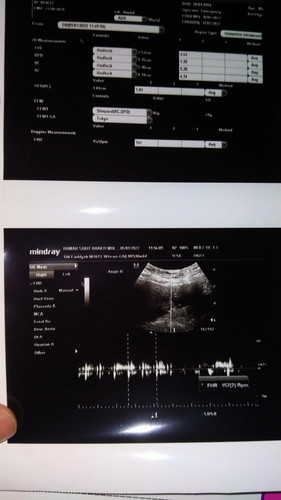

#bantusharing Bun apakah ada yg seperti saya usia kehamilan 10w dari 6w saya flek trs sudah USG baik baik saja,, dan USG ke 2 hari ini karena flek makin banyak menurut aku, tapi Alhamdulillah semua bagus dan sehat,, kali ada yg pernah ngalamin seperti saya agak takut sebenarnya 🥺 Makasih